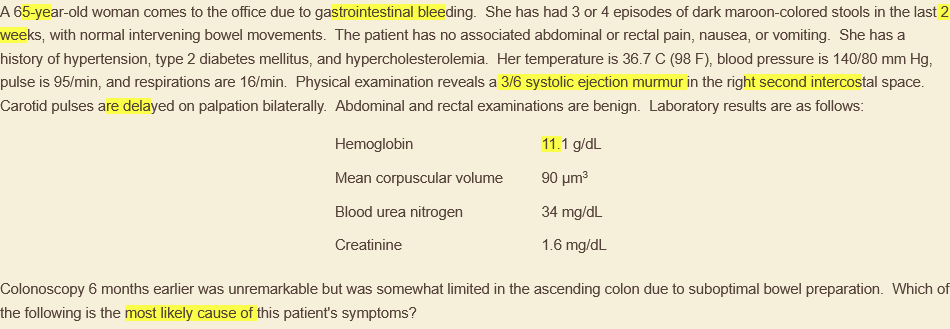

what heart murmur is related to angiodysplasia & why?

aortic stenosis, possibly due to acquired vWF deficiency (disruption of multimers passing through turbulent valve)

angiodysplasia = dilated submucosal beins & avms, ↑ after 60y; asymptomatic require no tx, otherwise endoscopic cautery